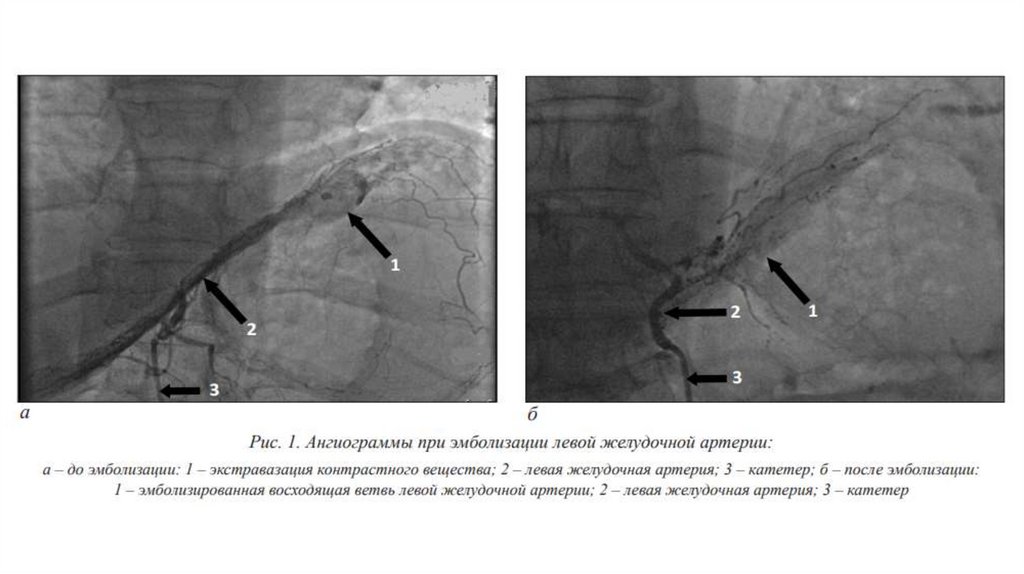

ТАЭ

Транскатетерную артериальную эмболизацию выполняется из бедренного

доступа. Последовательно производится селективная ангиографию

селезеночной, левой желудочной, желудочнодвенадцатиперстной артерии и

ее ветвей и ветвей верхней брыжеечной артерий с целью определения прямых

и косвенных ангиографических признаков кровотечения. К прямым признакам

относятся экстравазацию контрастированной крови, к косвенным тромботическую окклюзию сосудов, регионарный артериальный спазм,

аневризмы ветвей чревного ствола, а также признаки локальной

гиперваскуляризации и периартериальной диффузии контрастированной

крови. Далее выполняется локальную или сегментарную эмболизацию участка

или всего сосуда, являющегося источником кровотечения. В качестве эмбола

используется адгезивного клеевый композит разведенный с

рентгеноконтрастным веществом. Успехом ТАЭ считается отсутствие кровотока

в эмболизируемой артерии. После эмболизации для исключения кровотечения

из коллатеральных ветвей необходима контрольная ангиограмма чревного

ствола и верхней брыжеечной артерии.